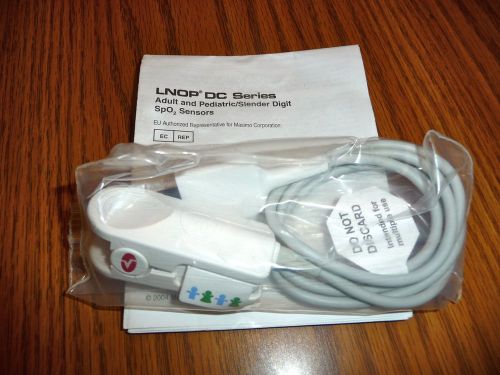

Masimo DC Series Adult and Pediatric/Slender Digit SpO2 Reusable Sensor

Masimo 14pins Compatible SpO2 Sensor Extension Adapter Cable

Masimo Reusable SpO2 Sensor Adult Finger Clip Sensor,3M, 14PINS